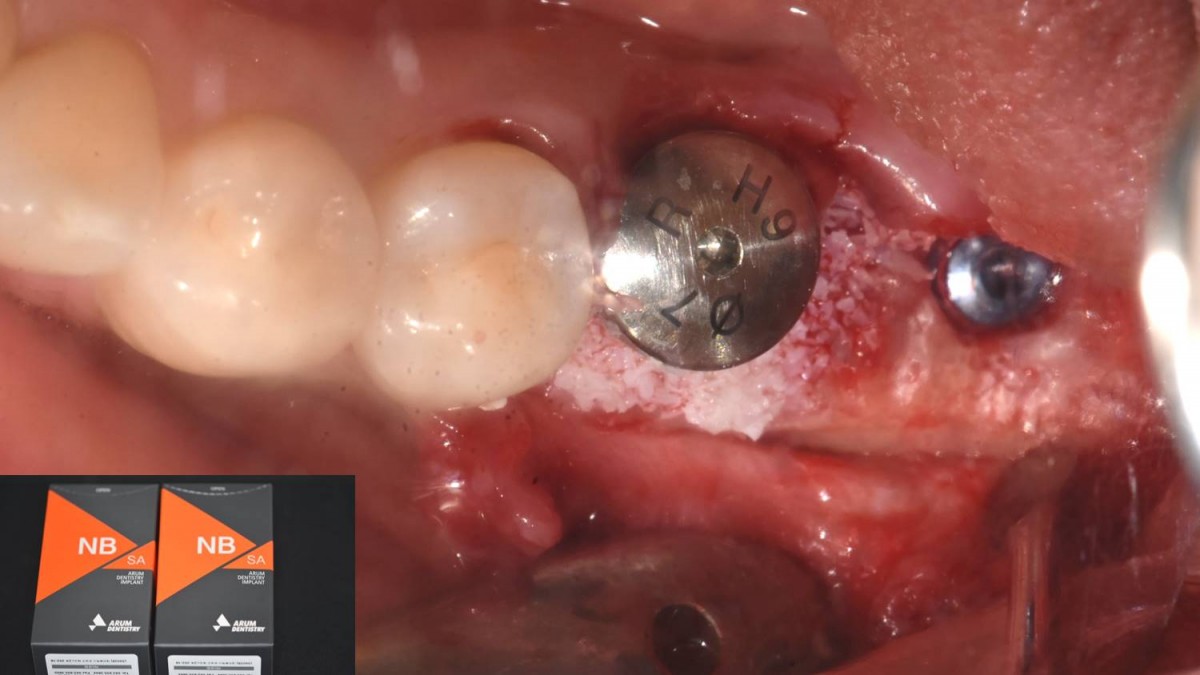

A 55-year-old female patient had

bilateral problems in both jaws.

It was decided to proceed with implant-supported restoration in the left molar part first.

She had been taking hypertension medication for a long time.